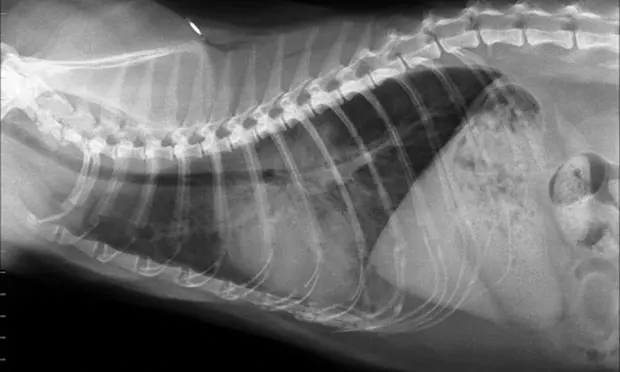

Feline lateral thoracic radiograph.

The following images exhibit commonly diagnosed emergency feline respiratory diseases. Match the image with the description of the disease process.